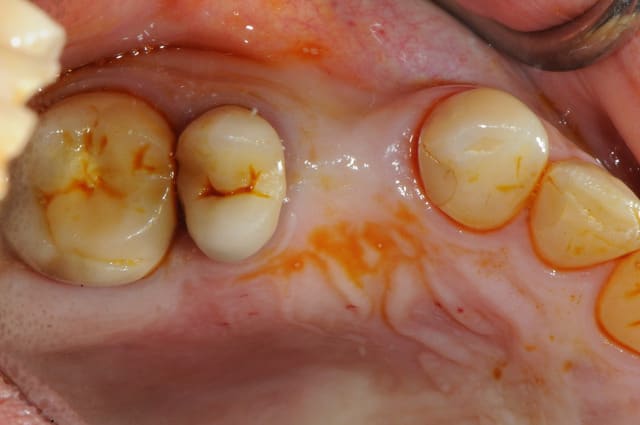

l’intérêt est surtout lié à la stabilité primaire puisque c'est un implant plus spécifiquement dédié aux MCI.

ici, tu l'as compris, ce n'est pas vraiment nécessaire excepté pour la 2 ième prémolaire où l'extraction est très récente (2 mois à peine) et où l'alvéole à été comblée par un biomatériaux.